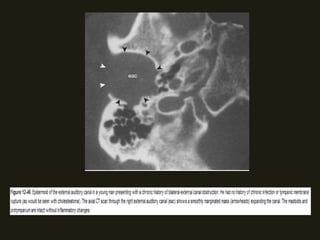

CISTOS EPIDERMÓIDES

• São massas de restos ectodérmicos embriônicos; podem

surgir em qlq parte do osso temporal;

• CAE – keratosis obturans;

• CAI – erosão óssea;

• São lesões expansivas císticas, bem definidas com contornos

nítidos;

• RM – hipointenso T1 e hiper T2, sem realce pelo contraste;

Difusão – hiperintenso;

• TC – hipodenso; pode simular cisto aracnóide; as lesões

podem ser sólidas e calcificadas;